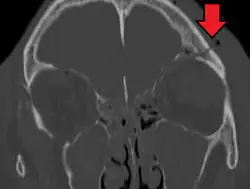

A basilar skull fracture as seen on CT

Basilar skull fractures include breaks in the posterior skull base or anterior skull base. The former involve the occipital bone, temporal bone, and portions of the sphenoid bone; the latter, superior portions of the sphenoid and ethmoid bones. The temporal bone fracture is encountered in 75% of all basilar skull fractures and may be longitudinal, transverse or mixed, depending on the course of the fracture line in relation to the longitudinal axis of the pyramid.[5]